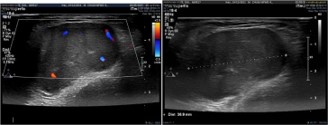

Ultrason showed a well-limited tissue mass of (39 × 23 × 21 mm) within the vascularized trapezius muscle on doppler (Figures 2).

Figure 2: Ultrason findings.